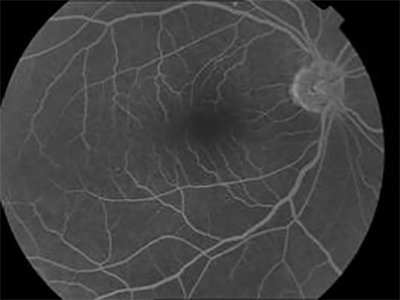

Fluorescein angiography

If your ophthalmologist finds an abnormality during an exam and suspects the wet form of AMD, he or she will take special photographs of your eye called fluorescein angiography (FFA). These photographs determine if abnormal blood vessels are under the retina.

To do this test, fluorescein dye is injected into a vein in your arm. The dye travels throughout the body, including your eyes. Photographs are taken of your eye as the dye passes through the retinal blood vessels. Abnormal areas will be highlighted by the dye, indicating to your doctor whether treatment is possible.

• expert AMD treatment doctors

Normal FFA

• best eye hospital for macular degeneration

FFA of AMD

• best retina hospital for macular degeneration

If treatment options are available, these photographs will provide your doctor with a map to guide the treatment